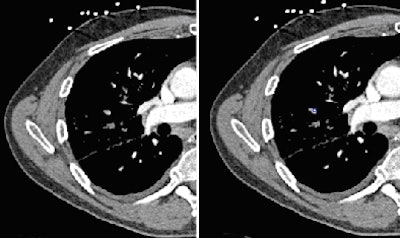

![]() |

| Notice both medial and lateral subsegmental PE (bottom right) found by CAD but missed by inexperienced readers. |